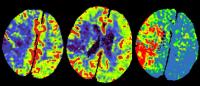

The study’s foundation is CT angiography (CTA)—a fast, widely available imaging tool that is already a routine part of the stroke workup at most major hospitals.

Rather than requiring a new or specialized scan, CAROTID-MAP aims to extract risk information from images already being obtained. The approach mirrors a transformation that reshaped preventive cardiology: in the coronary arteries, CT imaging has long enabled cardiologists to identify high-risk plaque features and predict heart attack risk before a clinical event, driving earlier and more targeted prevention. Despite the parallel anatomy and biology, a comparable CT-based risk framework has never been established for the carotid arteries.

The timing for this study is particularly good: a new generation of CT technology, photon counting CT, promises substantially higher spatial and contrast resolution and improved plaque tissue characterization, meaning the imaging foundation being laid by this study will only grow more powerful as the technology becomes more widely deployed.

Critically, CAROTID-MAP will pair that imaging foundation with artificial intelligence. Machine learning algorithms—including deep neural networks trained directly on CT pixel data—will be developed to automatically characterize high-risk plaque features and stratify stroke risk at a scale and speed that manual expert review alone cannot achieve. The algorithms will ultimately be tested in a prospective cohort of patients followed for recurrent stroke, with the goal of producing a validated, clinically deployable tool ready for multicenter trials.